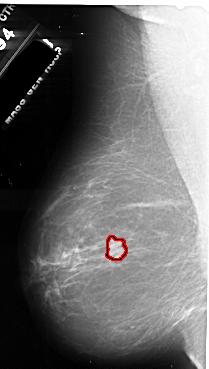

FILE: A_1055_1.LEFT_MLO.OVERLAY

TOTAL_ABNORMALITIES 1

ABNORMALITY 1

LESION_TYPE MASS SHAPE IRREGULAR MARGINS SPICULATED

ASSESSMENT 5

SUBTLETY 5

PATHOLOGY MALIGNANT

TOTAL_OUTLINES 1

BOUNDARY